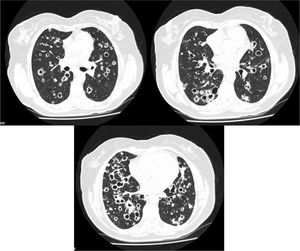

A 62 year-old female, former smoker (30 pack/year), with no relevant clinical history, presented with chronic dry cough, fatigue and weigh loss for 5 months. Her chest computed tomography (CT) scan showed multiple bilateral thin-walled air-filled cavities, with a diffuse distribution but basal predominance, round shaped but some of them with irregular borders, associated with centrilobular nodules (Fig. 1). She underwent flexible videobronchoscopy with no endoscopic abnormalities and a negative bronchoalveolar lavage (both cytological and microbiological analysis, including nucleic acid amplification test (NAAT) for Mycobacterium tuberculosis). Apart from positive antinuclear antibodies (ANA) and anti-Sjögren's-syndrome-related antigen A (SSA), blood analysis was irrelevant. The patient was then submitted to a surgical lung biopsy of the right lower lobe. Histological analysis of the biopsy showed multiple areas of mucinous adenocarcinoma. She was diagnosed with stage IV lung cancer and treated accordingly with chemotherapy.